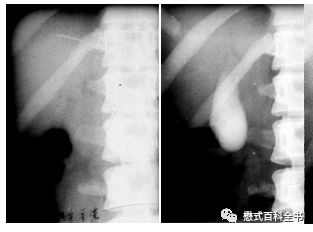

图4:X线胆囊造影(左边造影前、右边造影后)

扯回来,胆道系统影像学检查方法很多,除了前面说的MRCP和ERCP,还有X线胆囊造影,CT检查,超声等。不同检查方式有不同的优劣,本期内容我们就不重点讨论这个了。